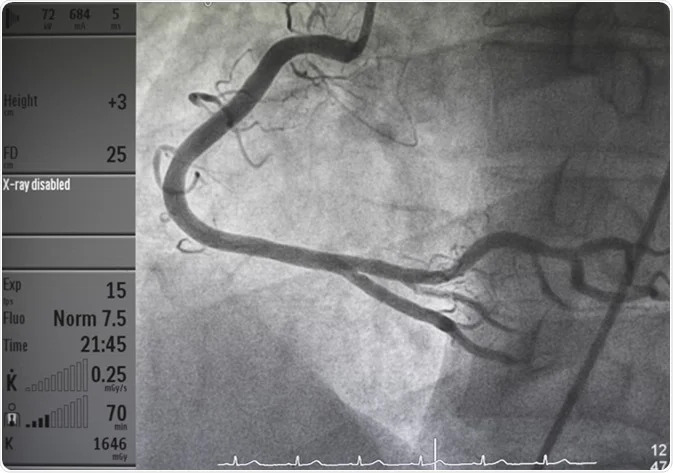

What is an Angiogram?

An ANGIOGRAM is an invasive procedure to find out whether or not there is a narrowing of the coronary arteries and how the heart is pumping. The procedure takes about half an hour in a cardiac catheter theatre. T he purpose of the procedure is to determine whether narrowing of the arteries has happened and if so to decide the most suitable treatment for the patient. NOTE. You will be asked to fast from midnight before this procedure. Ask your hospital for directions on taking any regular medications before your angiogram.